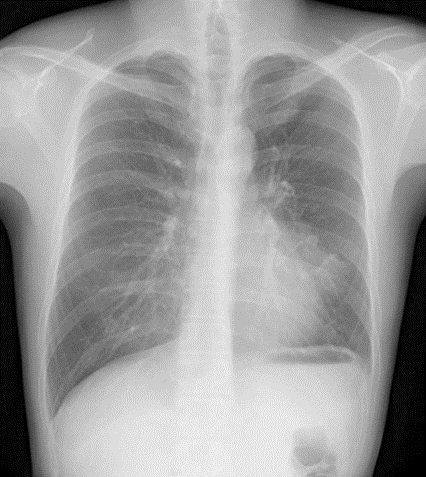

肺結核や非結核性抗酸菌症(NTM)を疑う胸部レントゲン(X-p)

肺結核や非結核性抗酸菌症(NTM)を疑うためには順番があり、まず肺炎を否定し、その後改善に乏しく精査にて疑う、という順番になります。今回は結果的には肺結核でしたが、そうは思わずまずレントゲンを見てください。

所見としては左舌区(左3弓シルエットサイン陽性)にコンソリデーションあり。

肺炎疑いです。

有症状であれば抗生剤投与適応になりますし、無症状であれば経過観察し改善乏しければ精査に進みます。改善認めずCT精査。